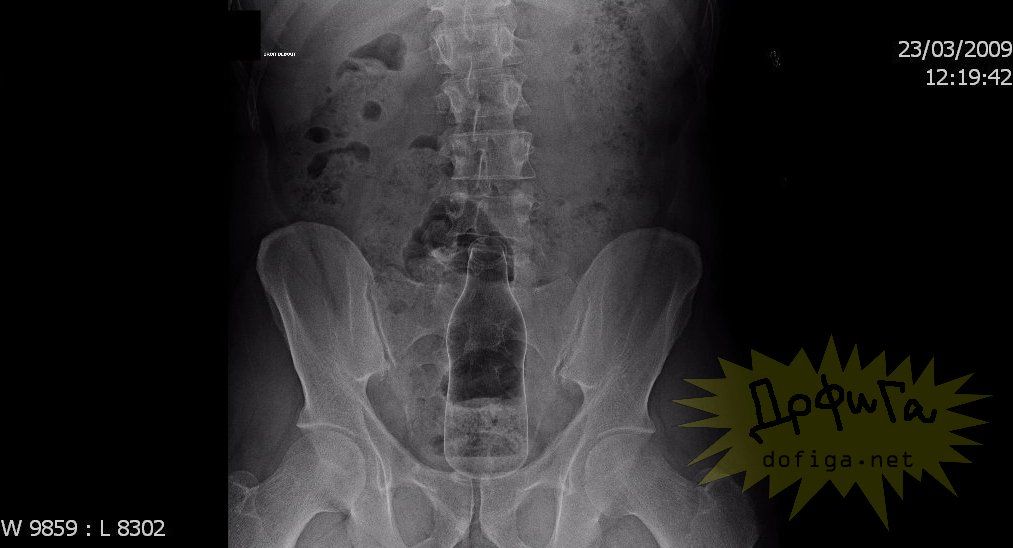

アナルに ”何かしら” を突っ込んで取れなくなってしまう人たちは意外に多いみたいで、そんな人たちのレントゲン写真を集めたギャラリー[13]images